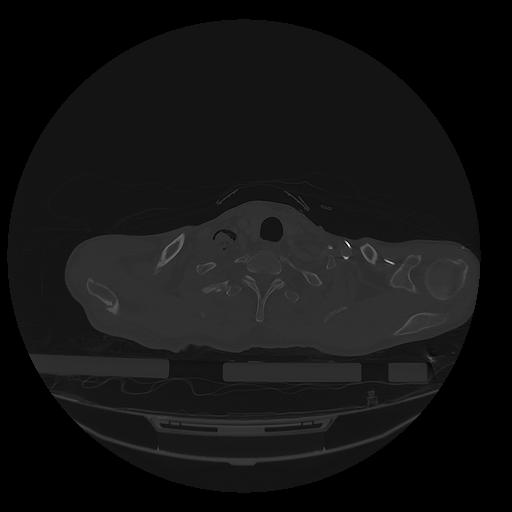

31 PULMON,CE,Vol,1.0,PULMON,,